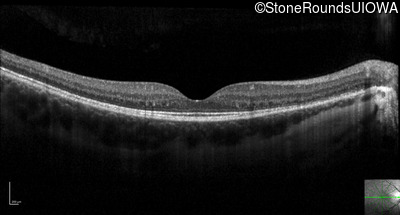

Optical Coherence Tomography - Left - 20/50

Exemplar / OCT Stack

OCT Stack